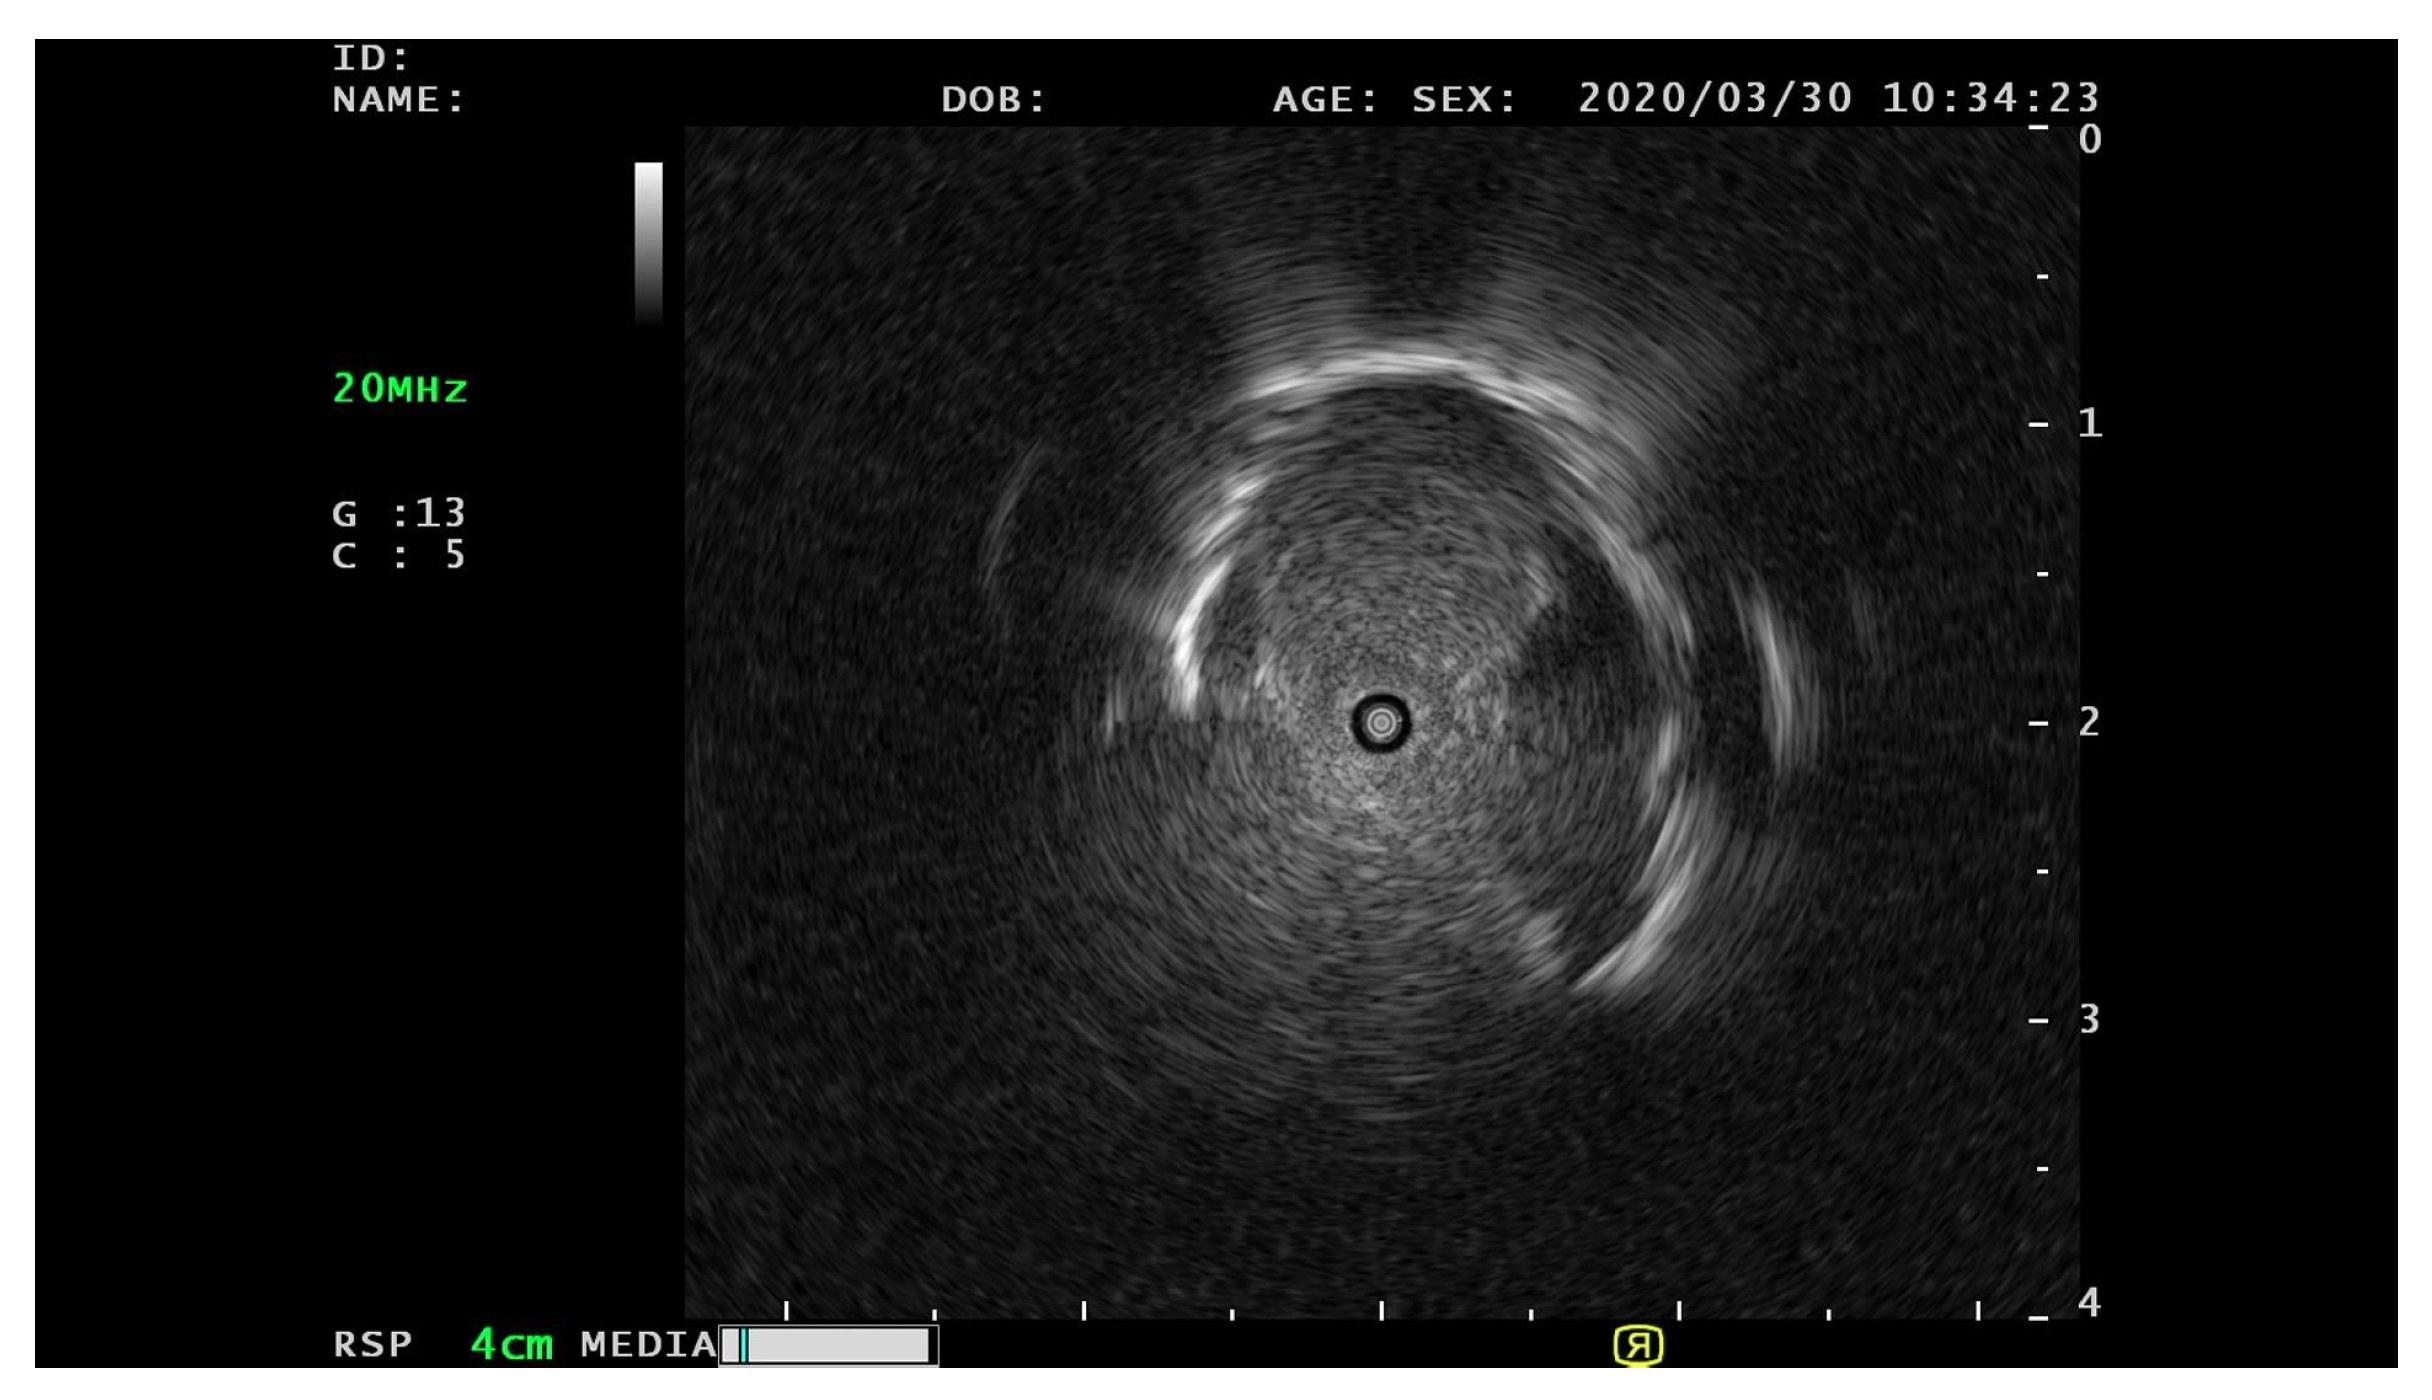

The EBUS images utilized in this particular study were obtained from Chiba University Hospital during the period spanning from September 2019 to April 2020. The acquisition of EBUS images was facilitated using an endoscopic ultrasound system (EU-M30; Olympus, Tokyo, Japan), along with a 20 MHz miniature radial probe (UM-S20-20R; Olympus). The miniature radial probe enabled a comprehensive 360° panoramic ultrasonic visualization of the peripheral pulmonary lesions. For the experimental data, a total of 71 patients were involved. The videos were saved in the Movie digital video technology (MOV) format. The EBUS images were in an 8-bit RGB format and each image was cropped to a size of 940 × 940 pixels. Figure 1 provides a visual representation of the various patterns of pulmonary lesions observed in the EBUS images.

Figure 3.

The example of the original EBUS image converted from the EBUS videos.